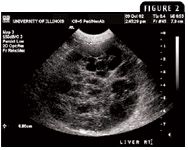

Abdominal ultrasonography is routinely used to identify hepatic parenchymal changes. When evaluating hepatic masses ultrasonographically, quantify and localize the masses, characterize their echogenicity, identify their distribution (solitary or diffuse), and look for evidence of cystic or vascular components. However, the ultrasonographic appearance of benign lesions such as nodular hyperplasia and many malignant lesions may be similar in dogs (Figures 3A & 3B).6-8 The difficulties in ultrasonographically differentiating between benign and malignant hepatic lesions have been recently reported. In one study, the ultrasonographic interpretation of 22 canine hepatic lesions resulted in a correct diagnosis in only 50% of cases, with more than 35% of focal benign lesions being ultrasonographically classified as neoplastic.9 Although the ultrasonographic appearances of hepatic lesions are often nonspecific, some studies have attempted to characterize ultrasonography findings most consistent with liver cancer. Some lesions identified ultrasonographically within visceral organs may take on a halo effect and are called target lesions because of a hypoechoic rim surrounding an isoechoic to hyperechoic center. Target lesions are associated with malignancy, with a positive predictive value of 74% for a focal lesion and 81% for multiple lesions.10

Figure 3A & 3B. Similar ultrasonographic appearances of a (3A) benign canine hepatocellular adenoma and (3B) malignant canine hepatocellular carcinoma (massive form). Both benign and malignant tumors produce sonographically evident mass effects, often appearing as mixed echogenic lesions.